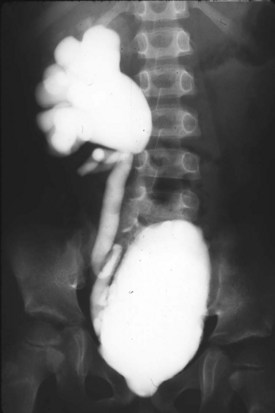

Today, most patients with posterior urethral valves are diagnosed with prenatal ultrasound. Obstruction leads to decreased fetal urine output and results in oligohydramnios. The observation of marked hydroureteronephrosis, a distended bladder, and a thickened bladder wall in utero strongly support the diagnosis of valves (Fig. 126–5). Often the urologist has been consulted long before delivery, and in some cases intervention has been undertaken in utero.

Figure 126–5 A, Ultrasound examination shows severe hydroureteronephrosis in a fetus with posterior urethral valves. B, Fetal ultrasound examination demonstrates a severely thickened bladder wall with a distended bladder and posterior urethra. These two fluid collections, a larger one above the smaller one, produce the “keyhole” sign indicative of posterior urethral valves.

The timing of screening for fetal uropathy is an important factor in accuracy. There is compelling evidence that valves may be missed if the screening ultrasound is done before 24 weeks’ gestation (Jee et al, 1993; Hutton et al, 1994). In Dinneen’s series, 92% of the 36 patients scanned before 24 weeks’ gestation were not detected. The classic ultrasound findings in patients with valves include bilateral hydroureteronephrosis, distended bladder, dilated posterior urethra, and a thickened bladder wall. The “keyhole” sign of a dilated bladder above a dilated prostatic urethra is also helpful. Bladder wall thickness is an important diagnostic sign. The findings of an excessively thick bladder wall and a distended bladder indicate distal obstruction (Kaefer et al, 1997a).